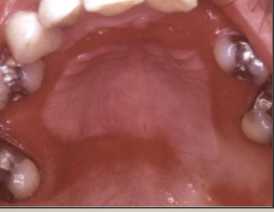

nicotine stomatitis

elevated papules with red central dots due to heat from smoking

false

T/F nicotine stomatitis is precancerous